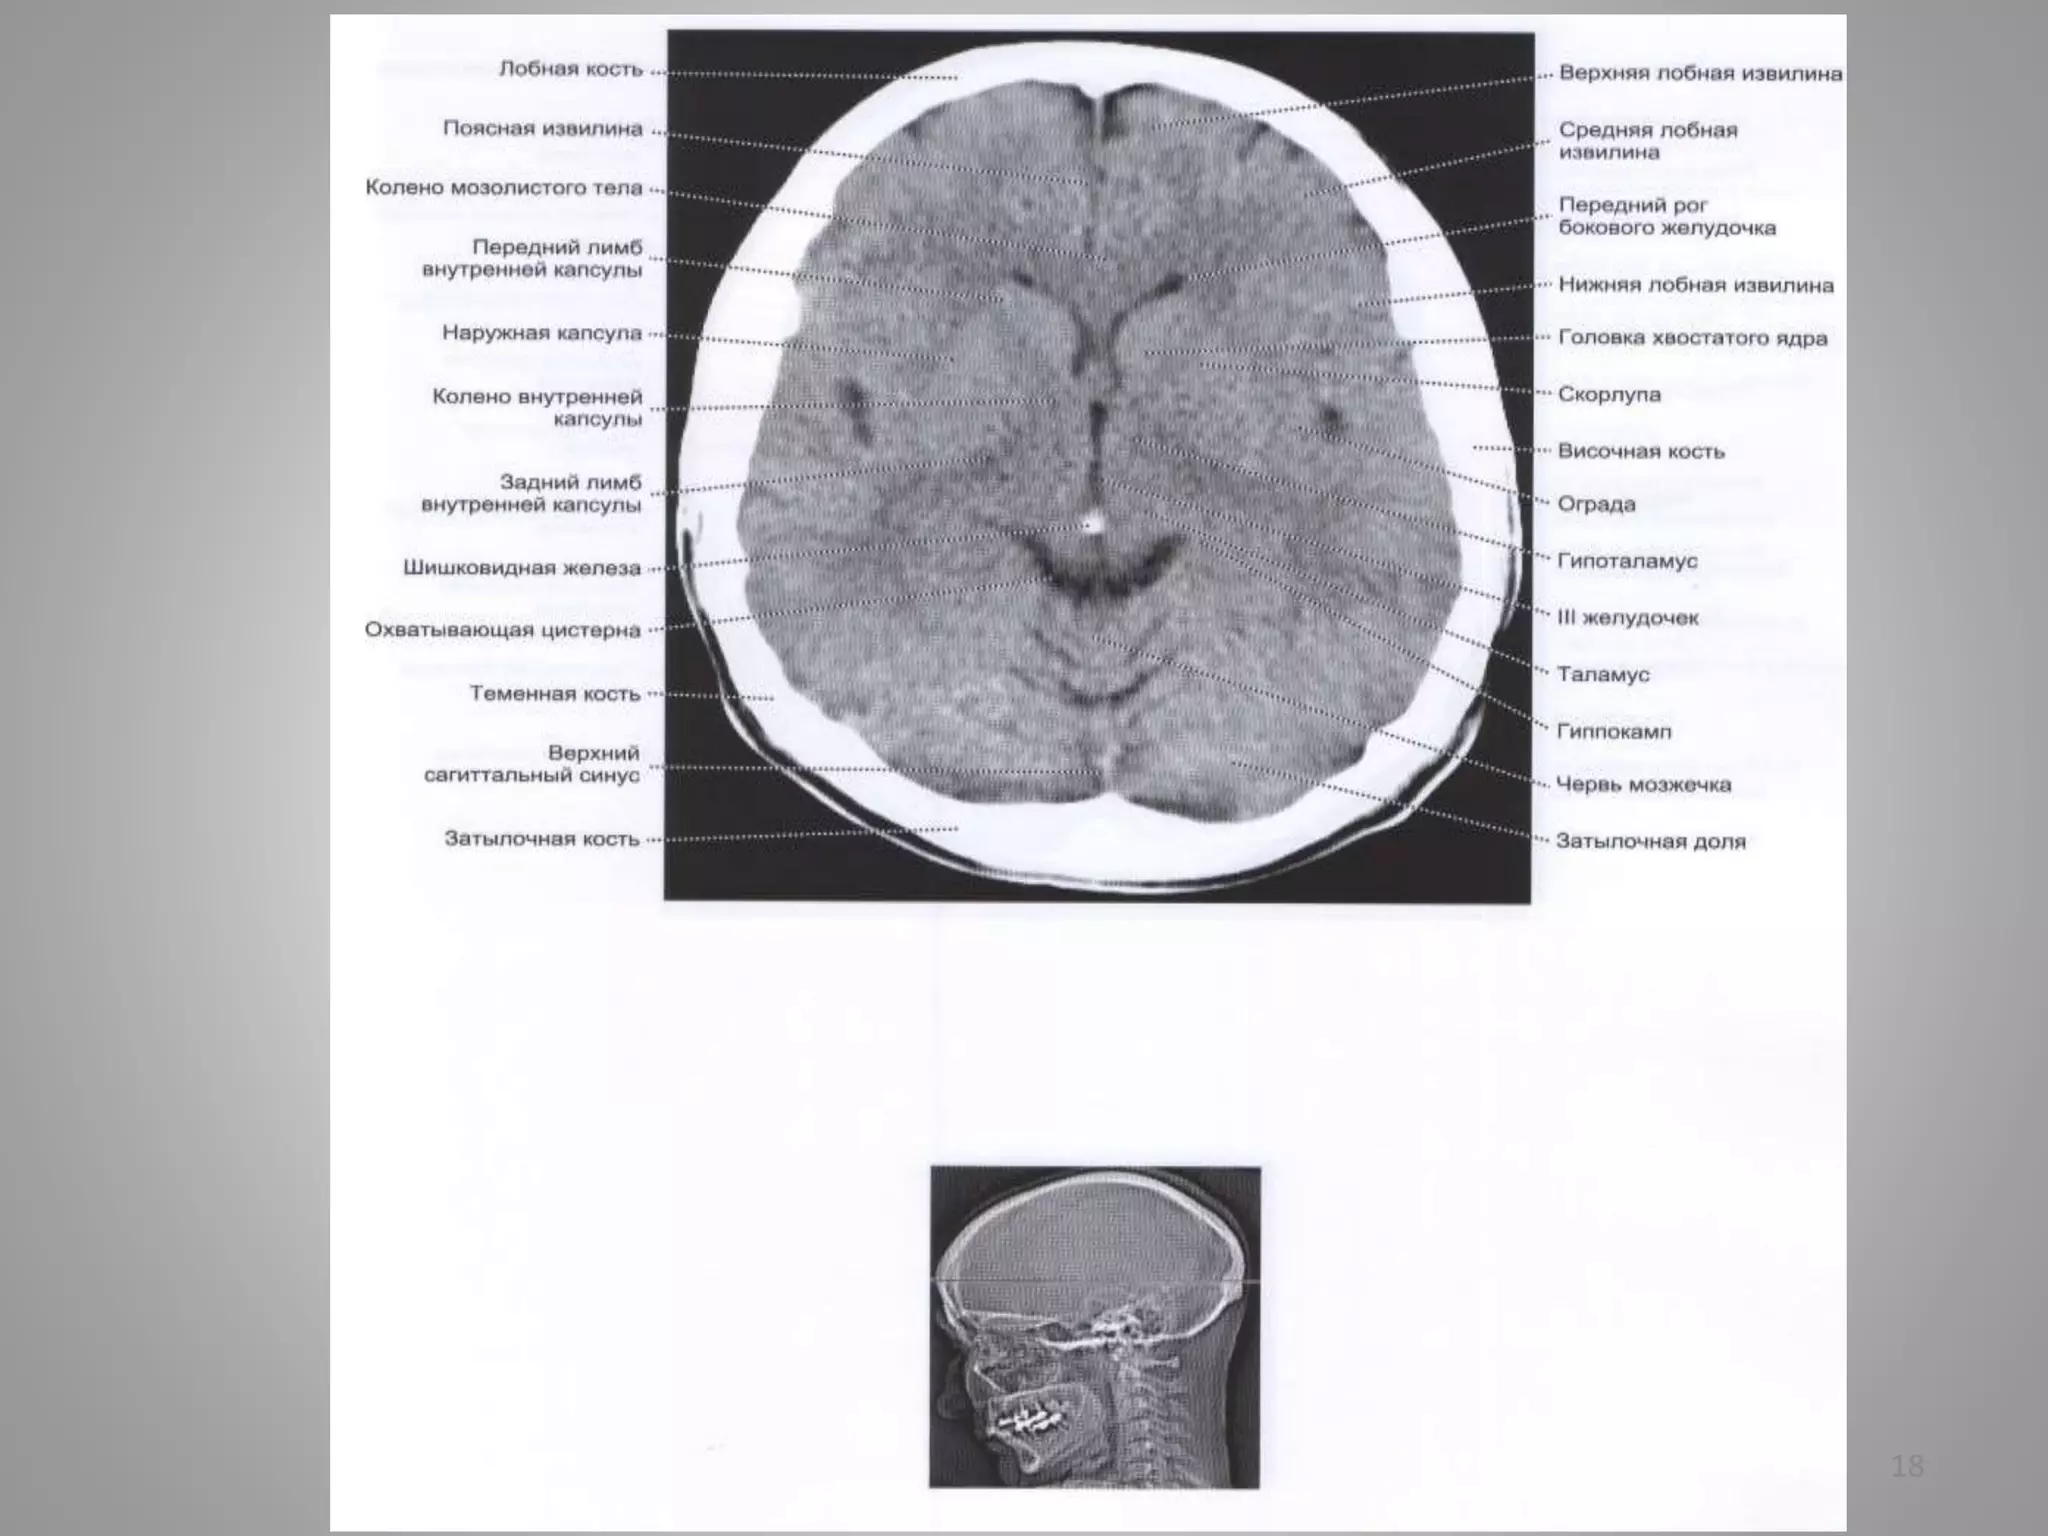

• 18.

• #18 Охоплююча цистерна

• #19 Охоплююча цистерна